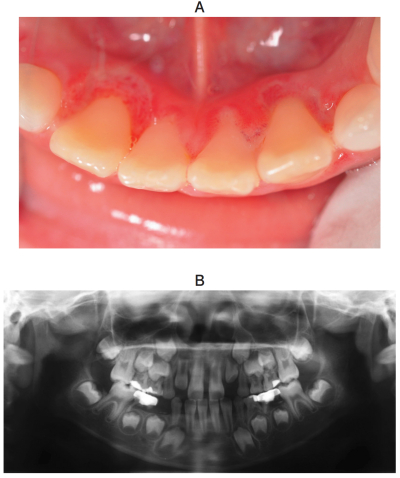

8歳の男児。歯肉の腫脹を主訴として来院した。日前から歯肉の激しい痛み、倦怠感および発熱があり、食事時には出血を伴うという。プラーク中の細菌検査では、スピロヘータと紡錘桿菌が多数検出された。初診時の口腔内写真とエックス線写真を別に示す。

疑われるのはどれか。1つ選べ。

e. 壊死性潰瘍性歯肉炎